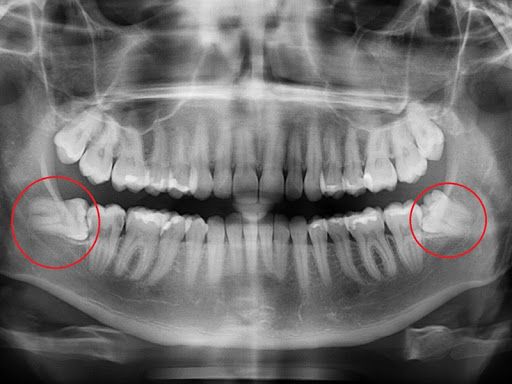

Răng khôn (răng số 8) thường gây ra nhiều phiền toái khi mọc lệch, mọc ngầm. Những cơn đau nhức dai dẳng, khó chịu khiến bạn lo lắng và sợ hãi. Đừng lo lắng, Nha khoa Mira sẽ giúp bạn giải quyết vấn đề này một cách nhẹ nhàng và hiệu quả.

- Gây đau nhức: Răng khôn mọc lệch, mọc ngầm chèn ép các răng bên cạnh, gây đau nhức âm ỉ hoặc dữ dội.

- Ảnh hưởng răng bên cạnh: Răng khôn mọc lệch có thể đâm vào răng số 7, gây sâu răng, lung lay răng.

- Biến chứng: Trong một số trường hợp, răng khôn có thể gây ra các biến chứng như u nang, tiêu xương.